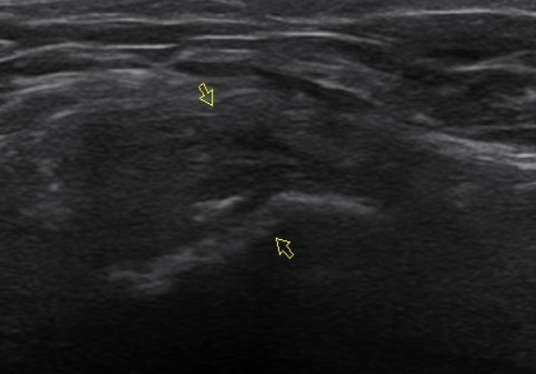

On retrouve à l’examen clinique une souffrance isolée des muscles adducteurs, le reste de l’examen est normal. Une échographie est réalisée chez ce patient montrant : une déchirure partielle du tendon du muscle long adducteur.

Le diagnostic est réalisé par l’examen clinique complété par l’échographie et/ou l’IRM si besoin. Nous pouvons voir sur l’image échographique la  déchirure partielle du tendon long adducteur.

Examen échographique réalisé à notre centre, retrouve la présence d’une tendinopathie du long adducteur compliquée d’une petite déchirure partielle